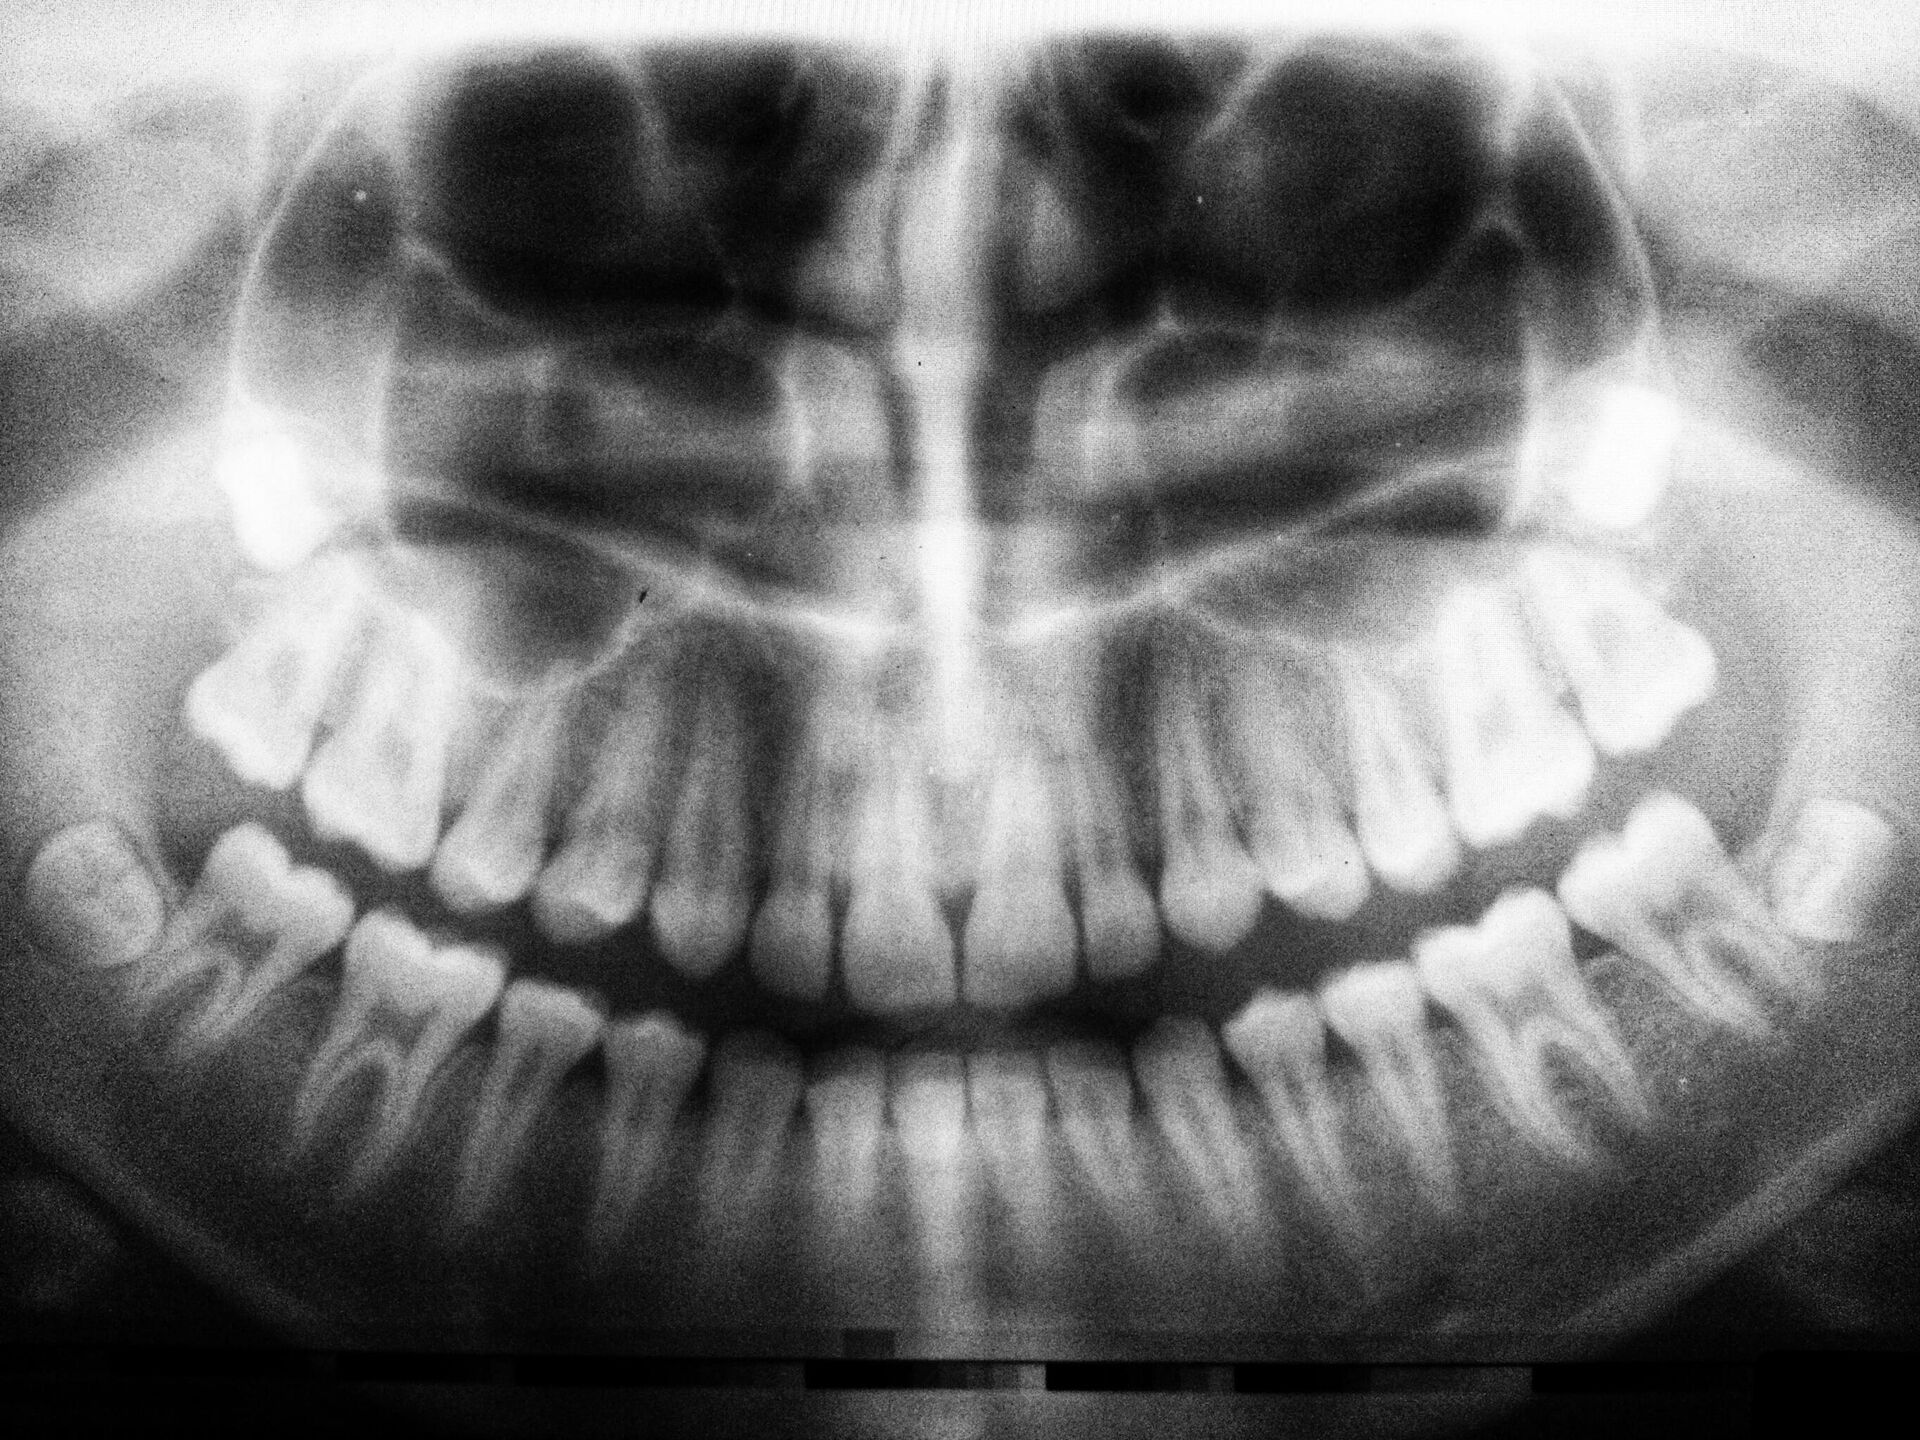

Muela del juicioEste molar es la octava muela de la fila, si contamos a partir de los dientes incisivos centrales. Cada persona tiene cuatro muelas del juicio. Dos de ellas se encuentran en el maxilar inferior y las otras dos en el superior. Estas molares recibieron este nombre específico debido a que aparecen mucho más tarde que las demás.¿Qué es una muela del juicio?Las muelas del juicio no se diferencian mucho de los demás molares. Si las comparamos entre sí en función de su ubicación en el maxilar superior e inferior, se destacan las siguientes características:• los molares inferiores de los ochos de ellos tienen numerosos canales de raíces;• debido a la mayor densidad ósea del maxilar inferior, los dientes son más difíciles de extraer.No existen otras características distintivas.Hay que señalar que dichos dientes se consideran órganos rudimentarios, es decir, aquellos que no tienen una determinada importancia para el organismo. Esto se debe a que en el proceso de evolución, el cuerpo humano experimentó algunos cambios, perdiendo algunas características innecesarias del mismo. La transición a la ingesta de alimentos más blandos y de mejor calidad hizo que las muelas del juicio fueran simplemente innecesarias.¿A qué edad es su aparición?Muchas personas creen que el momento en que aparecen estos molares no depende de la edad de la persona. Esto es un error: las raíces de la muela del juicio empiezan a formarse a los 15-17 años, y la muela del juicio en sí crece por término medio hasta los 30 años. A veces tiene su aparición un poco más tarde o un poco más temprano, y en ocasiones simplemente no aparece en absoluto.Los pacientes mayores de 30 años que acudieron al dentista pensando que les había salido una muela del juicio tenían más probabilidades de padecer pericoronaritis. Se trata de una inflamación de la parte de la encía que cubre la muela como si se tratase de una capucha a medio salir.Cuánto tarda en salirLa aparición de las muelas del juicio puede durar de uno a dos años, causando fuertes dolores.Desgraciadamente, no existe ninguna forma de acelerar su salida. El proceso de aparición puede llevar algún tiempo y depende de muchos factores, como la edad, si existe suficiente espacio dentro de la boca para que la muela aparezca, las características individuales de los dientes, etc.Síntomas de la aparición de las muelas del juicioNo siempre es así, pero es posible que las muelas del juicio salgan sin dolor. Sin embargo, a menudo el proceso va acompañado de molestias, así como de signos que incluyen:Complicaciones de la erupción de las muelas del juicioLos dentistas señalan una serie de razones que obstaculizan la aparición de las muelas del juicio:DiagnósticoEl médico elaborará un plan de tratamiento luego de examinar su salud bucodental y realizar algunas pruebas:Varios factores influyen en la elección de la táctica de tratamiento:Extracción de las muelas del juicioLa extracción de este molar se lleva a cavo con anestesia local o general. Depende del umbral de dolor del paciente, de su estado psicológico, así como de la complejidad de la operación. Además, el médico debe averiguar si el paciente tiene alguna intolerancia individual a determinados componentes del fármaco anestésico.La extracción de las muelas del juicio, como es de esperar, puede ser sencilla o compleja.Una extracción sencilla dura entre 5 y 10 minutos (sin contar el tiempo de espera hasta que haga efecto la anestesia). El médico simplemente afloja y luego saca la muela utilizando instrumentos especiales. Después se sutura o se tapa la herida.La necesidad de suturar es decisión del médico. Los especialistas experimentados prefieren no omitir esta etapa, porque reduce el riesgo de procesos inflamatorios en la cavidad bucal.Una extracción compleja se produce cuando el diente aún no ha erupcionado del todo o tiene las raíces torcidas y ramificadas. Asimismo, hay casos en los que la corona del molar está muy dañada, lo que dificulta bastante su agarre con fórceps.En algunos casos, luego de la anestesia, el médico tiene que hacer una incisión en el tejido gingival, así como perforar el tejido óseo o perforar el diente. Una extracción compleja necesariamente se completa con sutura.No se deben ingerir alimentos sólidos ni líquidos durante el tiempo recomendado por el especialista para permitir la coagulación de la sangre en la zona. Luego de la intervención, puede producirse hinchazón y dolor intenso al desaparecer el efecto de la anestesia. En este caso, es necesario tomar analgésicos recetados por el dentista.La zona de la extracción dental no debe tocarse con la mano ni con la lengua, y al comer debe utilizar otra parte de la boca. Debe abstenerse de fumar durante un día, ya que al hacerlo aumenta el sangrado. Se pueden aplicar compresas de hielo para aliviar la hinchazón. Si el daño en los dientes es más grave, se puede acudir a un dentista para que le informe sobre el método de implantación.Consejos del dentistaLa aparición de las muelas del juicio constituye un proceso biológico complejo. Este fenómeno tiene un impacto muy negativo en los tejidos blandos y óseos. Como resultado de las rupturas se produce inflamación, hinchazón, aumento de la temperatura del cuerpo o de la zona inflamada. También suele ir acompañada de una supuración grave. Cualquier proceso inflamatorio en la región maxilofacial conlleva consecuencias negativas y un gran peligro. Por lo tanto, si aparece dolor e inflamación, se recomienda acudir inmediatamente al médico.No puedes eliminar completamente el dolor por tu cuenta. Solo es posible aliviar sensaciones desagradables temporalmente en casa. He aquí algunas recomendaciones:

Este molar es la octava muela de la fila, si contamos a partir de los dientes incisivos centrales. Cada persona tiene cuatro muelas del juicio. Dos de ellas se encuentran en el maxilar inferior y las otras dos en el superior. Estas molares recibieron este nombre específico debido a que aparecen mucho más tarde que las demás.

¿Qué es una muela del juicio?

Las muelas del juicio no se diferencian mucho de los demás molares. Si las comparamos entre sí en función de su ubicación en el maxilar superior e inferior, se destacan las siguientes características:

• los molares inferiores de los ochos de ellos tienen numerosos canales de raíces;

• debido a la mayor densidad ósea del maxilar inferior, los dientes son más difíciles de extraer.

No existen otras características distintivas.

Hay que señalar que dichos dientes se consideran órganos rudimentarios, es decir, aquellos que no tienen una determinada importancia para el organismo. Esto se debe a que en el proceso de evolución, el cuerpo humano experimentó algunos cambios, perdiendo algunas características innecesarias del mismo. La transición a la ingesta de alimentos más blandos y de mejor calidad hizo que las muelas del juicio fueran simplemente innecesarias.

El médico elaborará un plan de tratamiento luego de examinar su salud bucodental y realizar algunas pruebas:

tomografía computarizada.